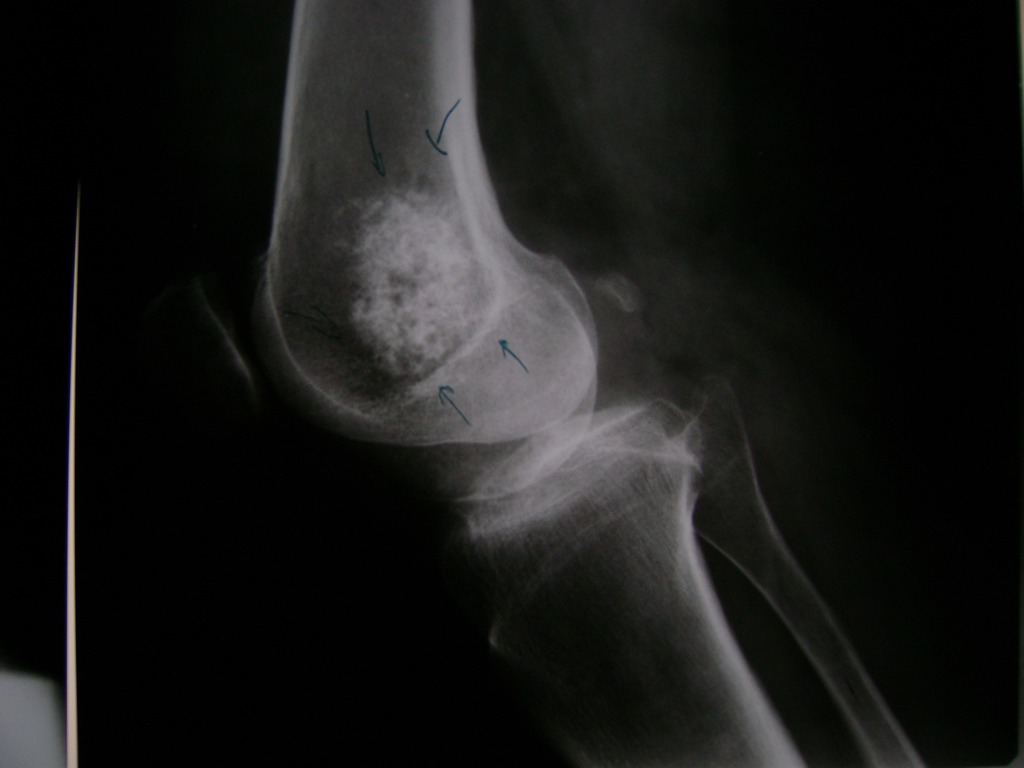

Cirugía de Fémur - Rodilla

La artroscopia de rodilla es un cirugía en el cual la estructura interna de la articulación es examinada ya sea para realizar un diagnostico o para realizar un tratamiento, este procedimiento se realiza utilizando un instrumento parecido a un pequeño tubo llamado artroscopio.